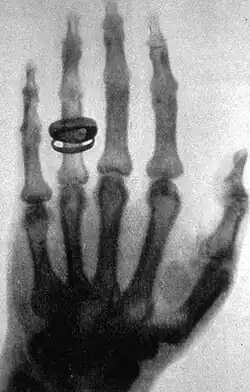

- X-rays. A form of electromagnetic radiation with a wavelength in the range of 10 to 0.01 nanometers, corresponding to frequencies in the range 30 to 3000 PHz (1015 hertz). X-rays are primarily used for diagnostic medical and industrial imaging as well as crystallography. X-rays are a form of ionizing radiation and as such can be dangerous.